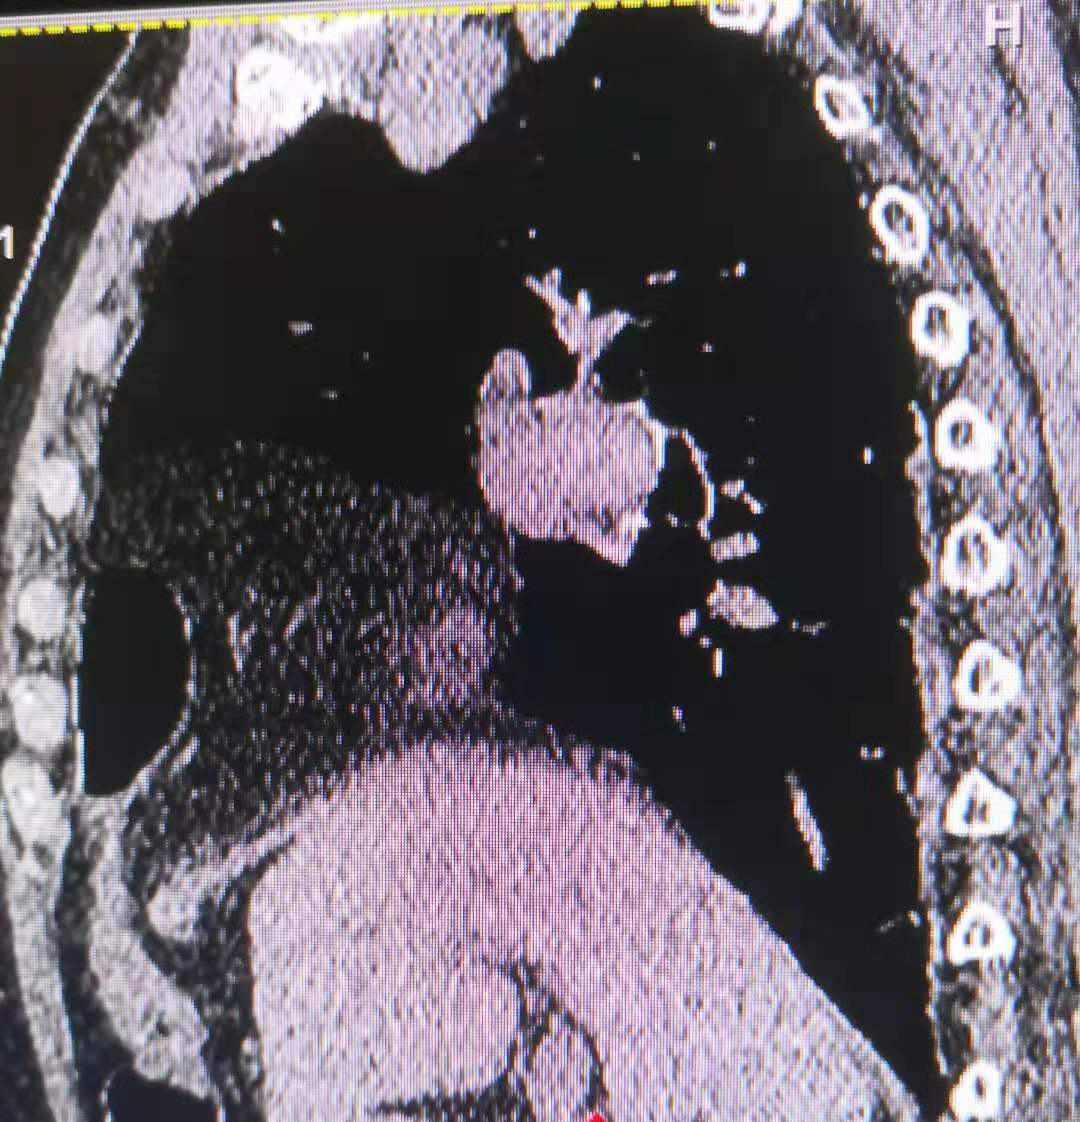

针对胸部的脂肪瘤,我院设备强大 的再重建功能显示,患者的膈肌上的巨大肿块影中有奇怪的积气现象。

往下追查,看到肿块来源于腹部,其中奇怪的气体影,是腹部的肠管。

最后的结论是腹部肠管及肠系膜疝入胸腔,患者长期的消化不良的现象得到了解释。